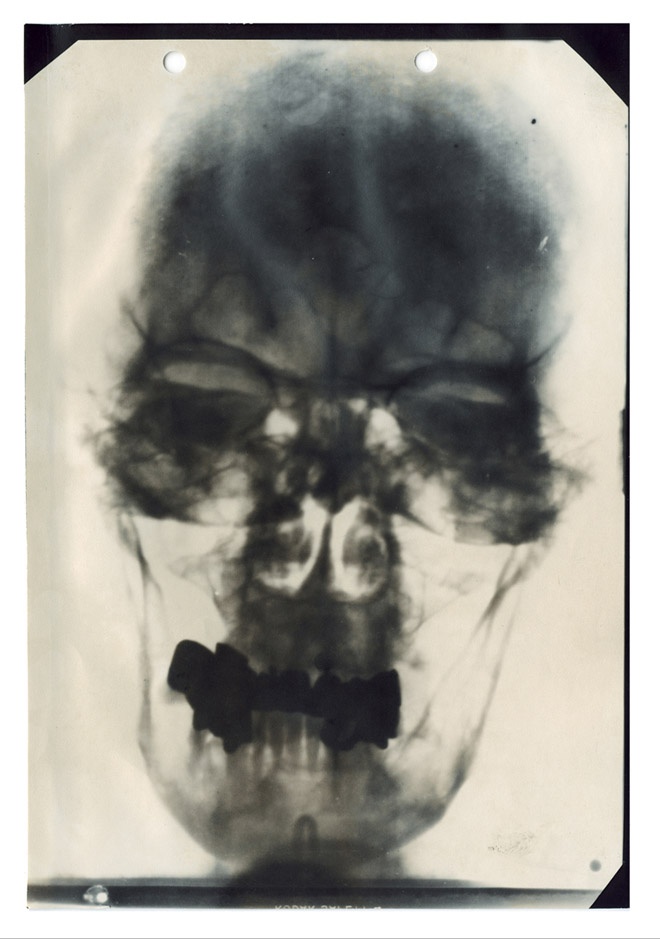

This is one of five known X-rays of Hitler’s head, part of his medical records compiled by American military intelligence after the German’s surrendered and declassified in 1958. The records also include doctor’s reports, diagrams of his teeth and nose and electrocardiograms. He had bad teeth, lots of fillings and crowns.